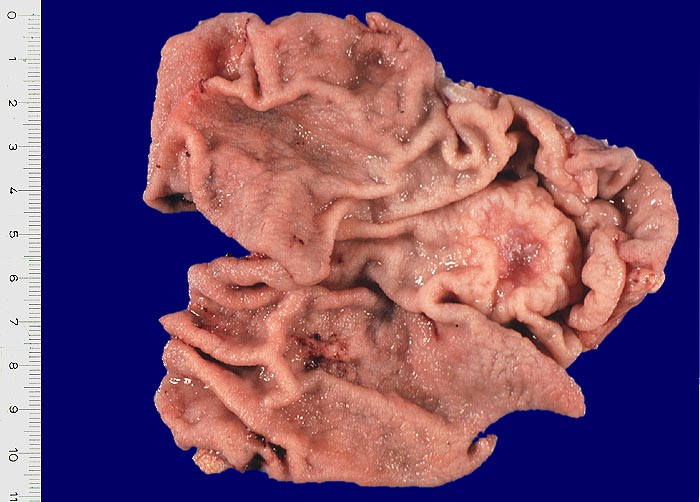

Das Magenfrühkarzinom ( 5049) ist durch die Beschränkung des neoplastischen Prozesses auf die Magenmukosa (Mukosatyp) oder auf die Mukosa und Submukosa (Submukosatyp) definiert, unabhängig von der Flächenausdehnung und unabhängig vom Lymphknotenstatus. Die Muscularis propria des Magens ist dabei tumorfrei, was nur nach kompletter histologischer Aufarbeitung des Tumors bewiesen werden kann. Die Diagnose Magenfrühkarzinom kann daher präoperativ im Biopsiematerial nur vermutet werden und muß im Operationspräparat verifiziert werden.

Bei Magenfrühkarzinomen findet sich häufiger ein intestinaler als ein diffuser Typ nach Lauren (Magenkarzinom vom diffusen Typ siehe Differentialdiagnose). Beim intestinalen Typ ist das Tumorgewebe relativ scharf gegenüber der Umgebung abgegrenzt und zeigt meist tubuläre Tumorformationen, die von Zylinderepithel ausgekleidet werden. In der Nachbarschaft von Magenkarzinomen des intestinalen Typs finden sich gehäuft Dysplasien als sogenannte Ausläuferläsionen oder schwere Formen der chronisch atrophen Gastritis mit intestinaler Metaplasie ( 1302).

Bei längerer Transportdauer Gastrektomiepräparat vor der Fixation in 10% Formaldehyd an der großen Kurvatur eröffnen und auf einer Styroporplatte aufspannen.

Die Resektionsränder und bei Verdacht auf Magenfrühkarzinom zusätzlich das Tumorareal am unfixierten Präparat mit Faden markieren, da das Auffinden von Resektaträndern und Frühkarzinomen am formolfixierten Präparat oft schwierig ist.